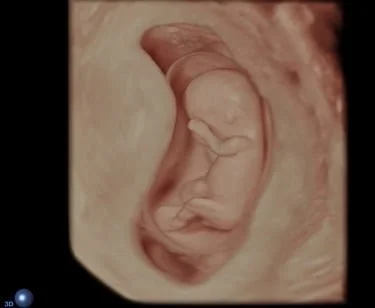

kombiniertes Ersttrimesterscreening mit Risikoberechnung für früh in der Schwangerschaft auftretende Bluthochdruckkomplikationen sowie die häufigsten Chromosomenstörungen beim Kind zwischen 11+0 – 13+6 SSW. Diese Untersuchung beinhaltet immer auch eine frühe Fehlbildungsdiagnostik des Kindes.

Ich arbeite mit einem „High-End-Ultraschallgerät“ der neuesten Generation, welches speziell für Pränataldiagnostik und Frauenheilkunde entwickelt wurde.